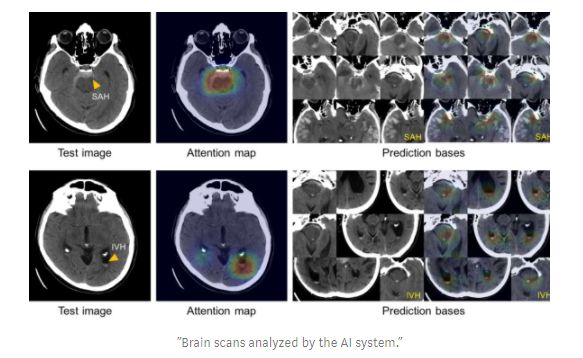

今年还见证了ML在健康应用方面令人难以置信的进步。例如,马萨诸塞州的研究人员开发了一种人工智能系统,能够像人类一样准确地发现脑出血。

https://venturebeat.com/2019/01/04/massachusetts-generals-ai-can-spot-brain-hemorrhages-as-accurately-as-humans/